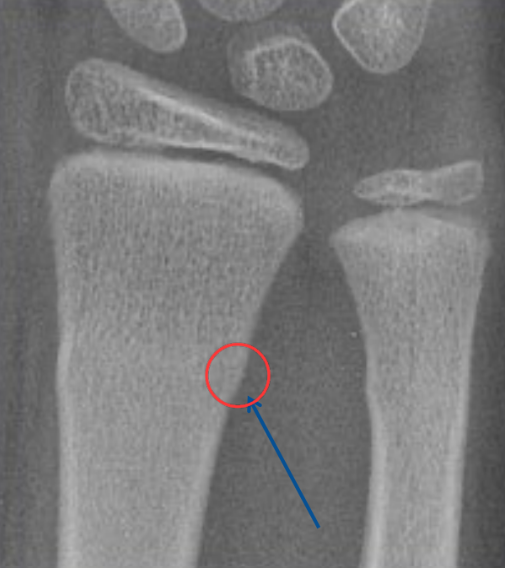

Q

A

torus (fx ped)